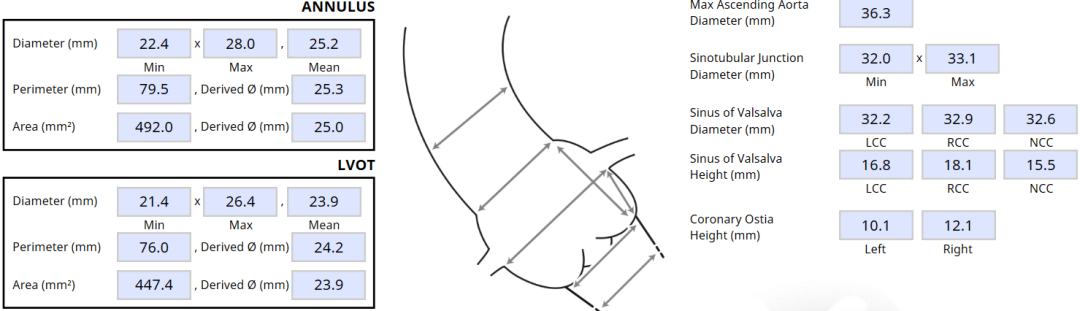

瓣环及左室流出道:

主动脉瓣根部:

LCA 10.1mm,瓣叶长度16.8mm;RCA 12.1mm,瓣叶长度18.1mm:

左冠近端见钙化,STJ见钙化:

该患者瓣环最小径22.4mm,且瓣叶重度钙化,此外左无冠窦之间有一处柱状钙化延伸至LVOT,决定术中用20mm球囊预扩,评估冠脉风险和指导瓣膜选型。此外,患者双侧瓣叶长度均大于冠脉高度,且左冠团状钙化,冠脉遮挡高危,拟在TAVR前行左冠支架保护。